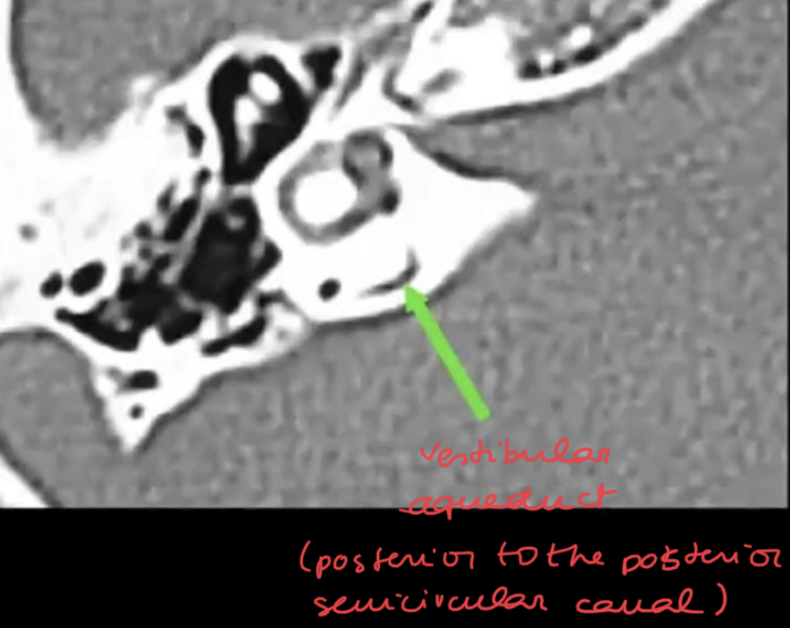

Above which width you consider a pathological vestibular aqueduct?

Whats the main associated symptom?

?